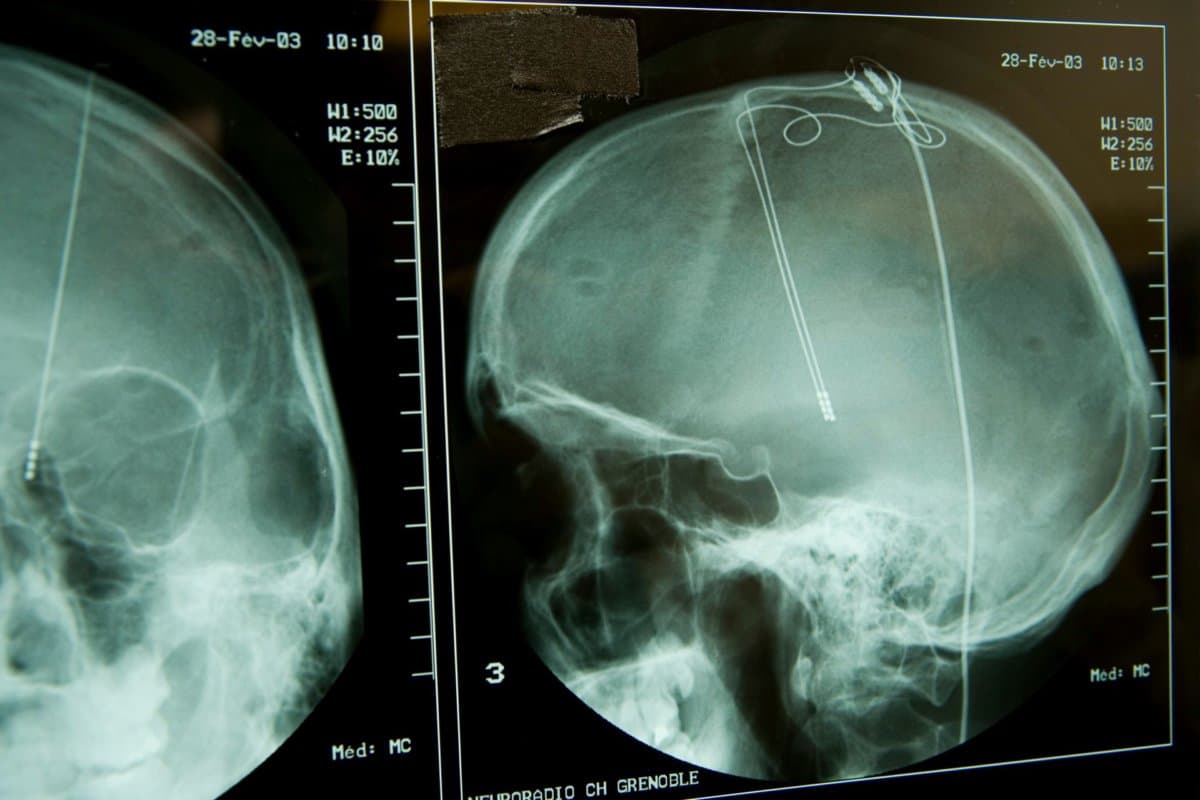

Bei der Tiefen Hirnstimulation werden Elektroden in definierte Kerngebiete des Gehirns implantiert, wo sie schwache hochfrequente elektrische Impulse aussenden. Die Steuerung der Impulse erfolgt von einem Schrittmacher aus, der meistens im Bauch- oder Brustbereich implantiert und über ein Kabel unter der Haut mit der Elektrode verbunden ist.

Den Teilnehmern wurden je vier Elektroden in die fronto-striatalen Regionen implantiert, um die striatofrontalen Verbindungskerne (centrolateraler Thalamus) und -fasern (mediodosaler tegmentaler Trakt) zu stimulieren.